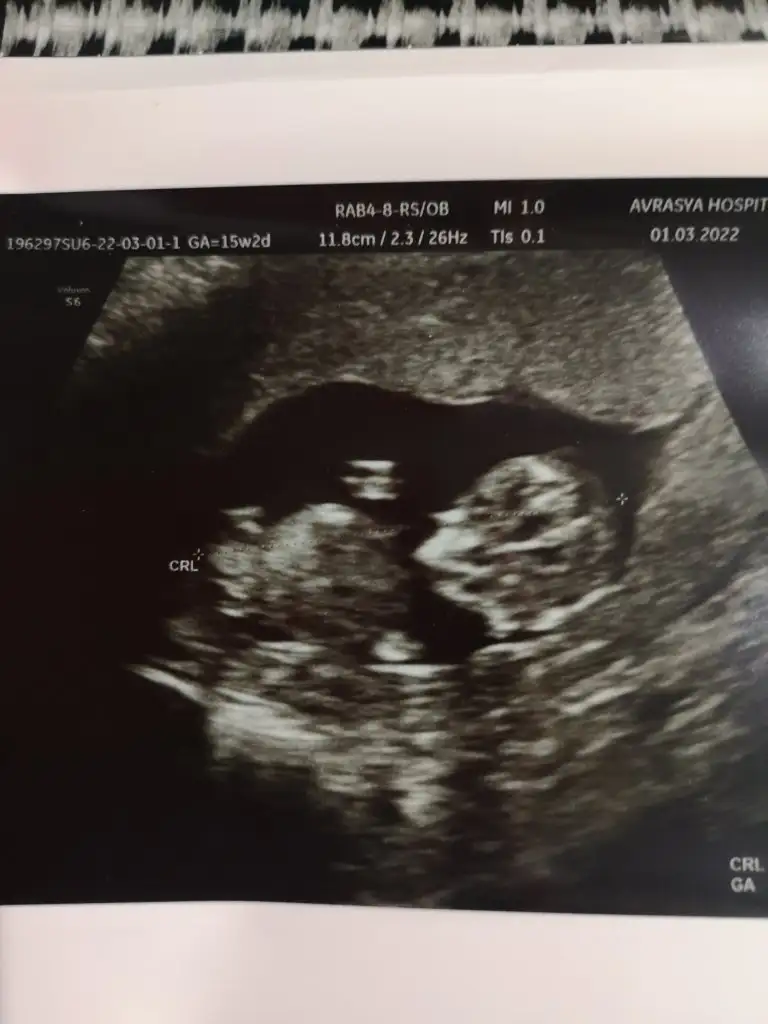

5+1 karından :) çok merak ettim şimdi :)

• 8DB33A59-29FE-4F9C-98AE-B869E6E79A20.webp

8DB33A59-29FE-4F9C-98AE-B869E6E79A20.webp

24,1 KB · Görüntüleme: 115